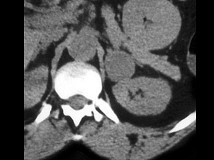

患者偶然发现肾上腺团块,结合所示图像,最可能的诊断是()

• A.转移

• B.脂肪瘤

• C.腺瘤

• D.嗜铬细胞瘤

• E.以上都不是